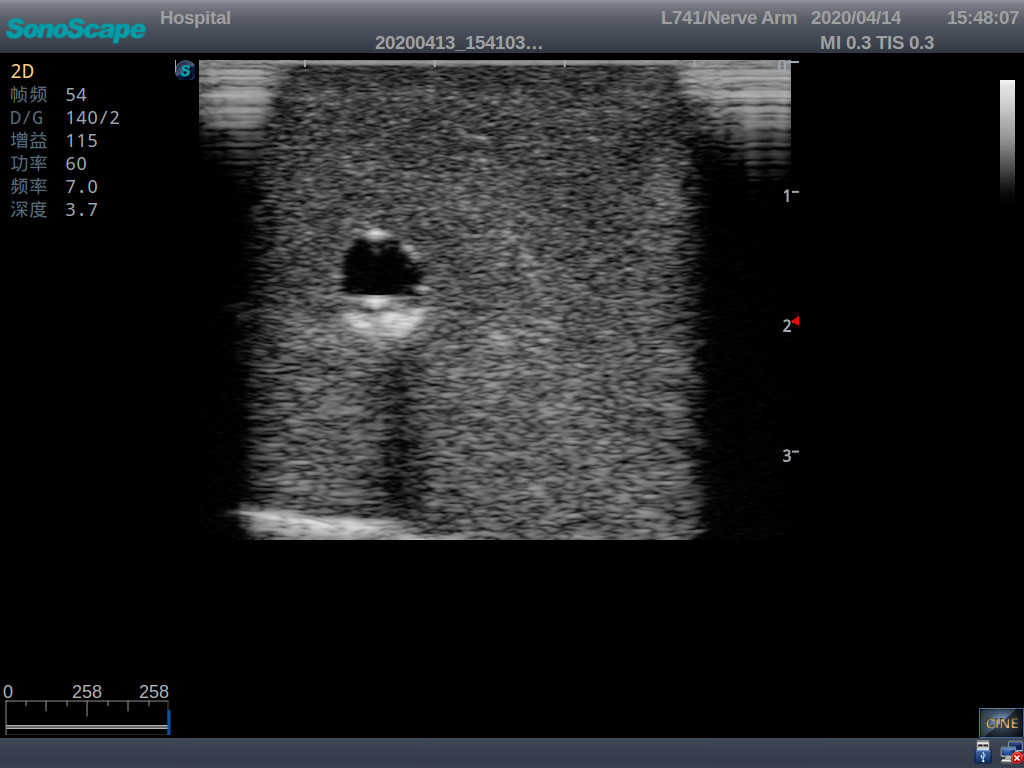

4) When conducting vascular puncture, the piercing can be truly felt, and venous blood outflow can be seen

5) Observe the guide wire marches

6) Detect whether the catheter is properly placed